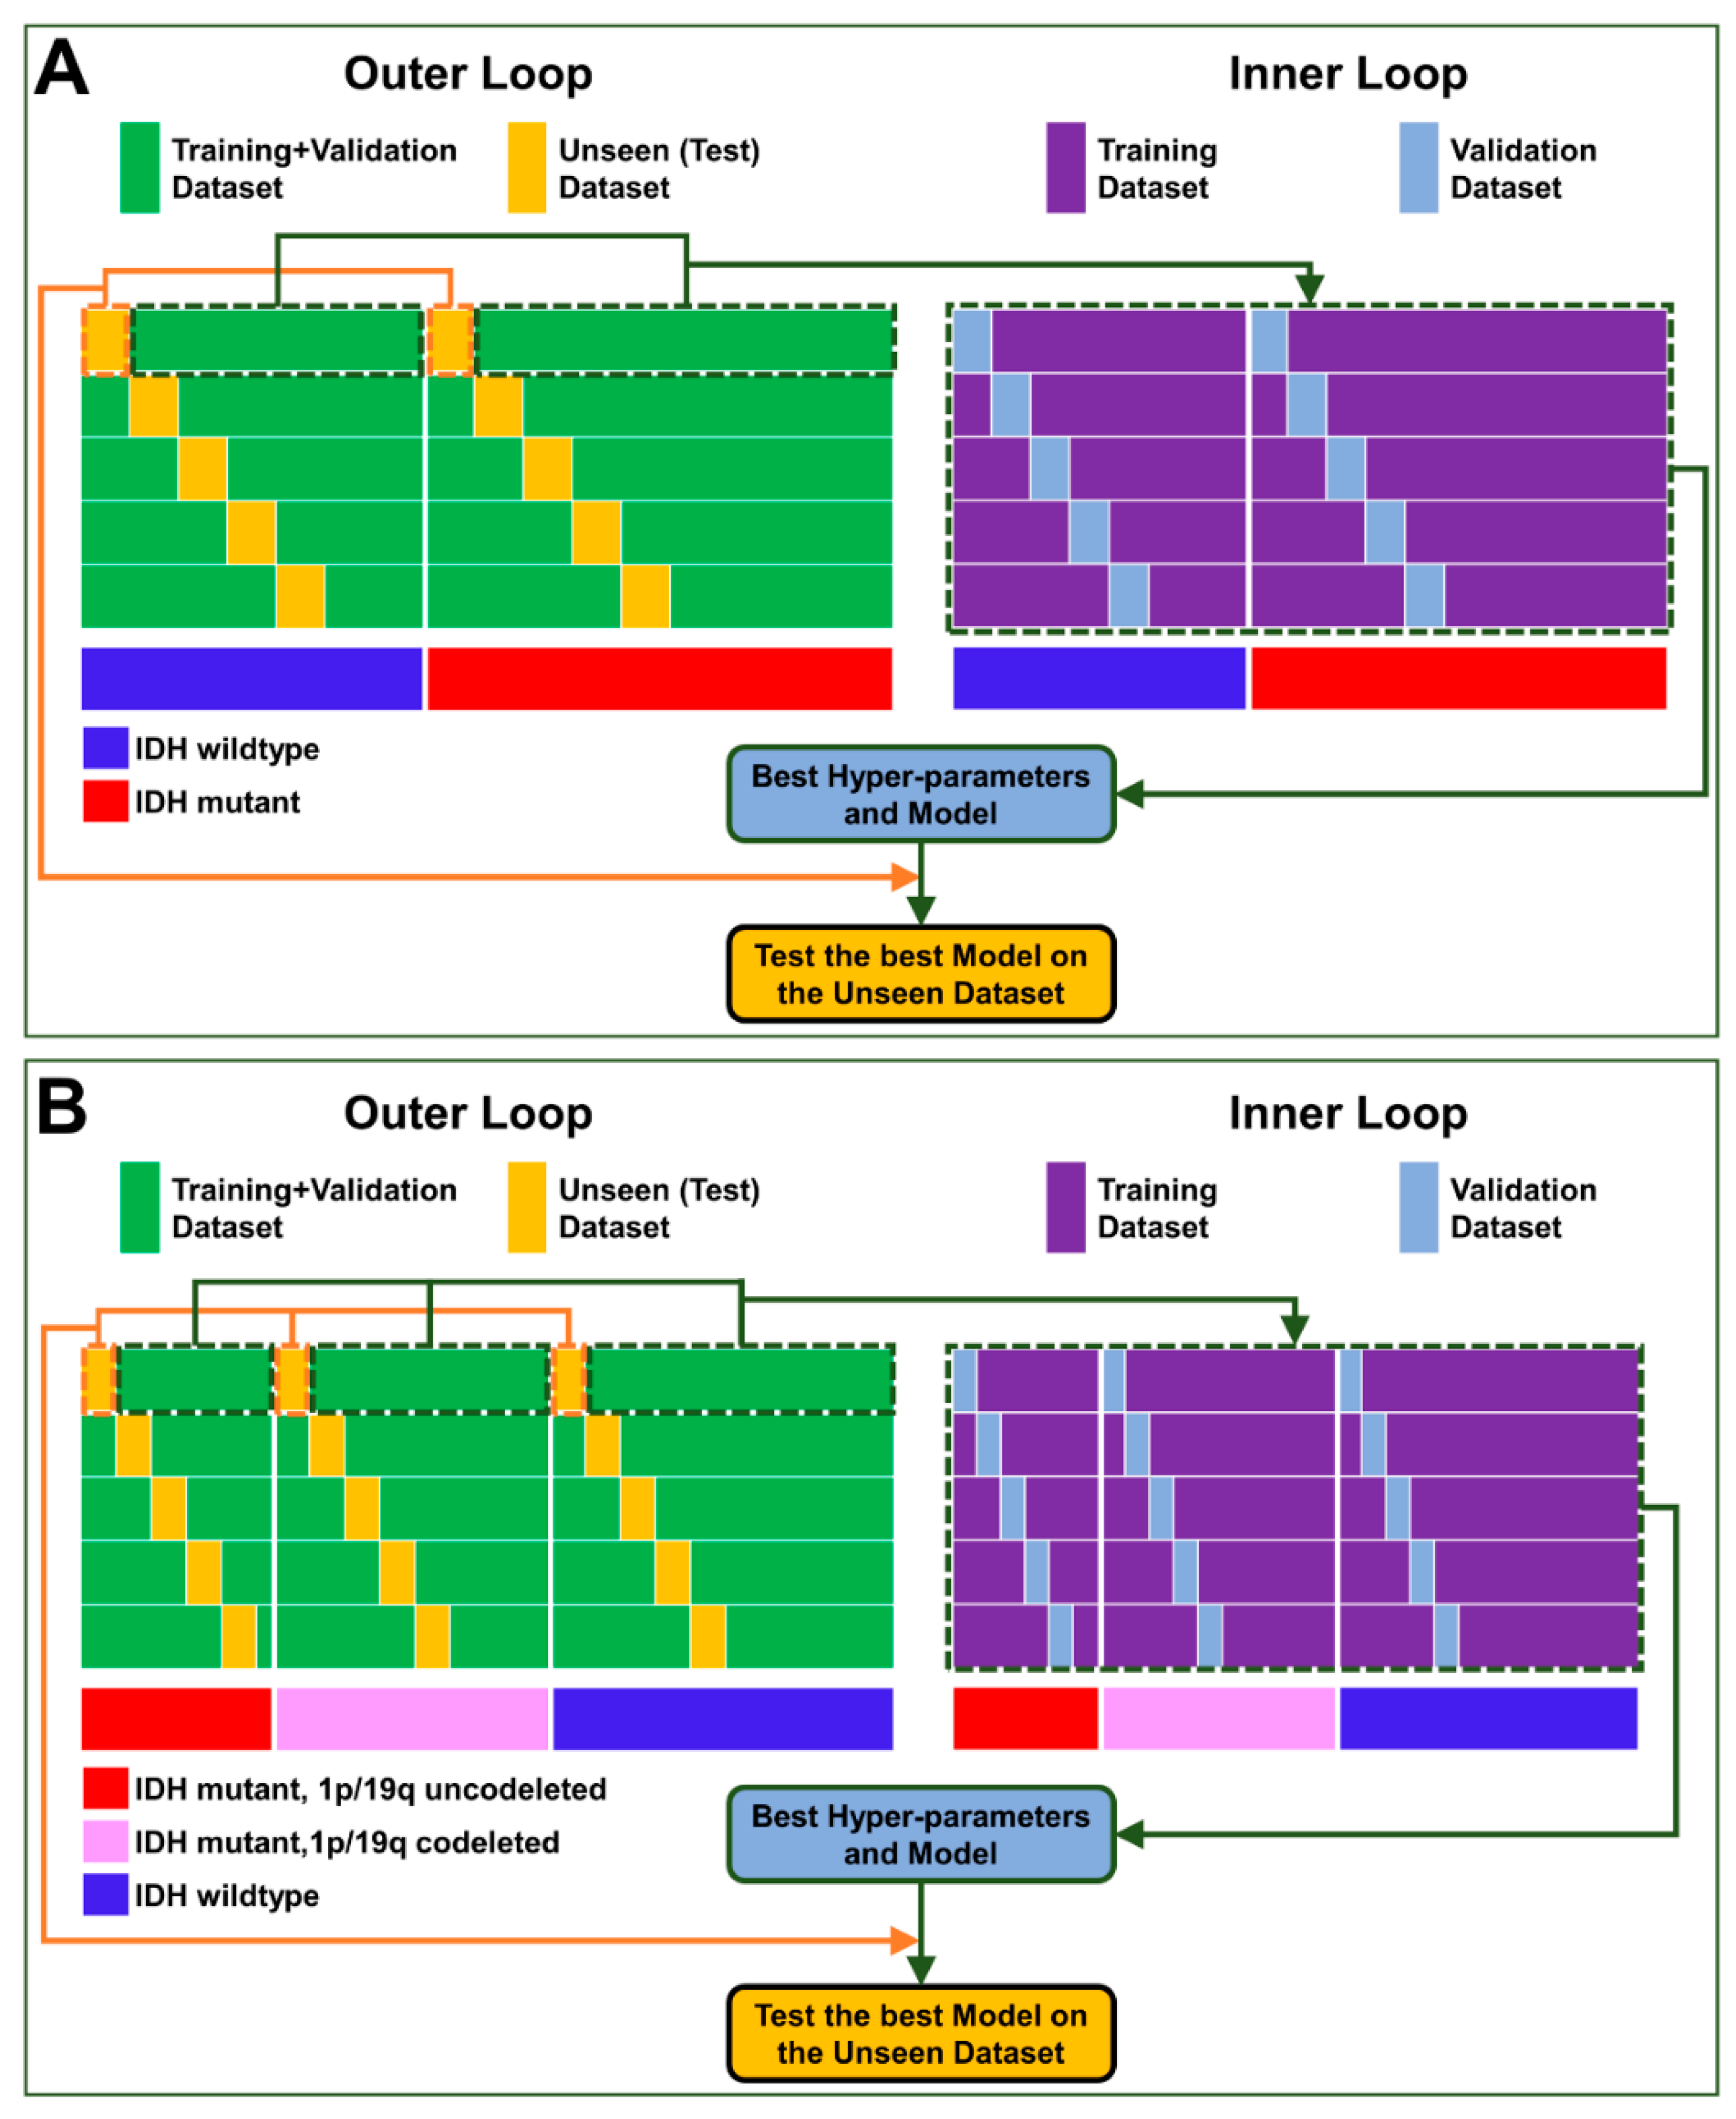

2.1. Experimental Design

2.5. ResNet Architecture Description and Model Development